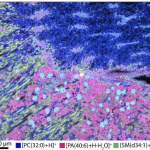

- This is a MADLI/MxIF image showing proteins & cells in the kidney made by HuBMAP researcher Allison Esselmen that won the “Image of the Poster Session” award at last week’s NIH-CZI Junior Investigators Meeting. Left side – MALDI-IMS of glomeruli, blue in background is the autofluorescence overlayed on top Right side – MxIF Magenta – podocytes, yellow – mesangial cells, teal – epithelial cells in proximal tubules, dark blue – vascular smooth muscle cells